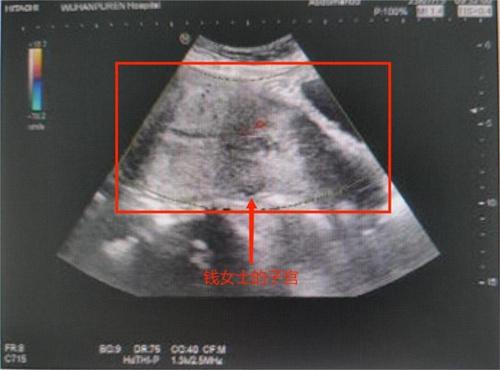

38歲的錢女士以為自己是例假不調不到,前幾日在家中自己排出一個巴掌大的肉團。急忙趕到武漢市普仁醫院產科就醫,發現自己已經流產了,痛失了自己在腹中的寶寶,感覺到極為后悔。

7月10日錢女士覺得自己下腹隱隱作痛,但因為痛感并不強,并沒有做出有關的處理,4月14日晚上8點,錢女士腹痛突然加劇,有著墜脹的感覺。晚上10:30左右將一個血乎乎的肉團排了出來,只是以為自己肚子疼,想去上廁所,結果一下把自己嚇懵了,在檢查后發現這一個肉團是已經滿了24周的胎兒。

之前已經切除過一邊輸卵管,加上個人有點胖,肚子也看不出來,沒辦法想到自己已經又懷孕了,之前僅僅以為是月經不調,由于錢女士宮腔中仍然有胎盤,還沒有清理排出,婦產科醫生也為錢女士安排了無痛清宮的手術。目前僅僅是在整個恢復情況上是良好的,由于肥胖對于女性,卵巢以及身體功能會產生影響,所以患者對自己兩次出血是先兆流產的表現也不清楚誤以為是月經不調導致的。如果早點前往醫院檢查,并且科學不要配合治療后,孩子是完全可以等到足月分娩下來的。